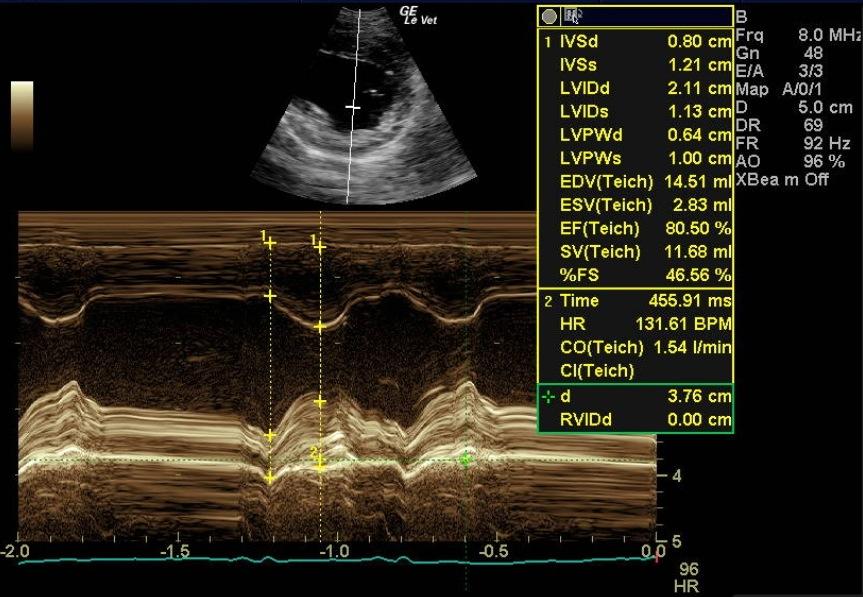

A 1-year-old female spayed toy poodle dog presented for evaluation of bradycardia. Blood pressure was within normal limits. Survey thorax radiographs showed normal size and shape of the cardiac silhouette and left atrium. The vertebral heart sum was 10.2, and a mild interstitial lung pattern was noted.